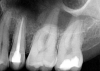

Fig 1. A preoperative radiograph was taken, the patient was administered local anesthetic, and a digital estimated measurement was recorded for initial working length.

Figure 1

A patient presented with acute pain and facial swelling. Tooth No. 6 was positive to percussion, without sensitivity to air, sweets, or temperature stimulus. Treatment options were discussed with the patient. The decision was to complete endodontic therapy to eliminate the pain (Figure 1). Definitive long-term final-restoration treatment options were presented using a fiber post and core with full-coverage CAD/CAM crown.